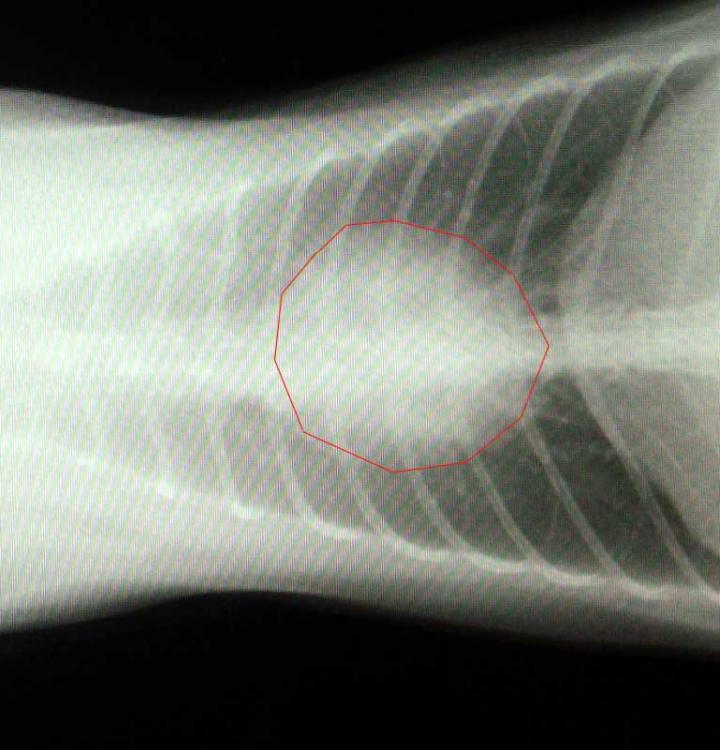

心臓の拡大です。

形が丸くなってハート型じゃなくなってます(^O^)

超音波で心筋の厚さとかを計測した結果、正常値で異常なし!

血液検査もほぼ規定値ないで問題ありませんでした。

心電図も不整脈等もなく綺麗な波形とでした!!

以後は特に異常がなければ検査の必要はないとのことでした。(定期検査を除く)